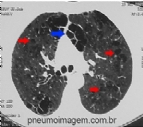

NOVAS DROGAS PROMISSORAS EM FIBROSE PULMONAR IDIOPÁTICA

Resultados com novas drogas em Fibrose Pulmonar Idiopática (FPI) divulgados ontem na Conferência Anual da American Thoracic Society, que está sendo realizada em San Diego, oferecem uma nova esperança para uma condição que tem um prognóstico...